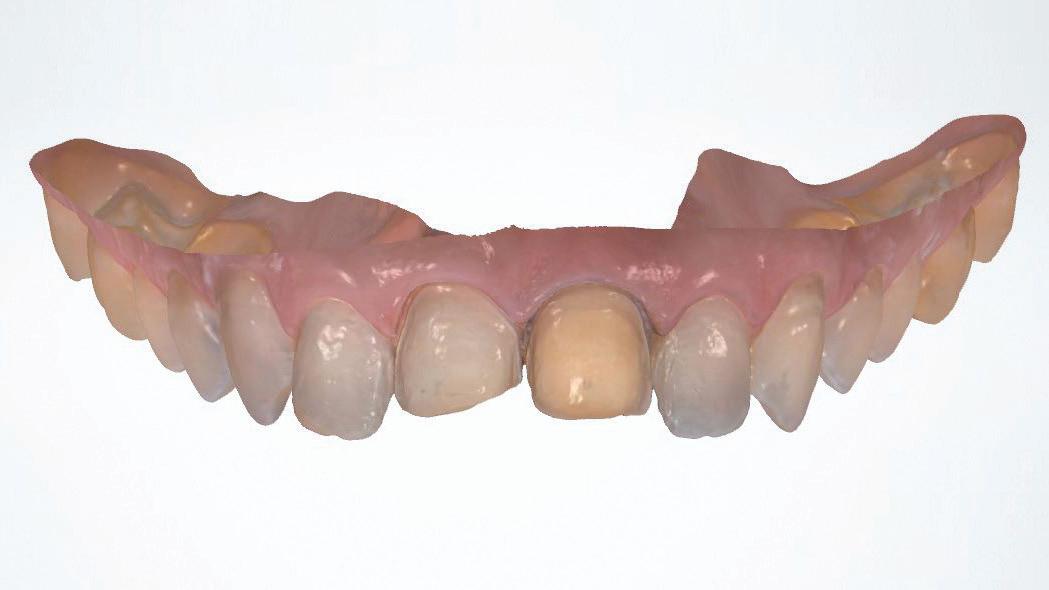

Seamless integration with new DTX Studio™ Clinic software

P acked with AI-assisted software features, DTX Studio™ Clinic complements OP 3D LX in numerous ways—for example, correcting patient positioning errors and detecting

landmarks, annotating mandibular nerve canals, tracing patientspecific panoramic curves for mandible and maxilla and merging CBCT and intraoral scan data for improved implant planning. These intuitive award-winning software features support a more efficient workflow allowing you to spend less time in the software and more time with your patient.